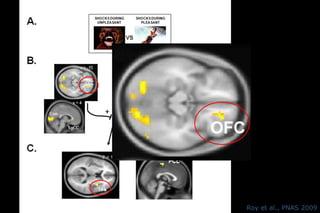

Roy et al., PNAS 2009

Modulation de la douleur par les émotions